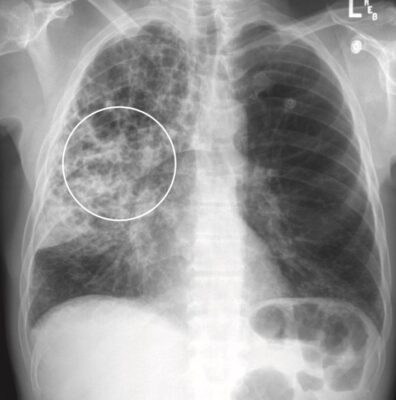

Phù phế nang phổi (Pulmonary alveolar edema)

- Phù phế nang phổi cấp tính điển hình thường tạo ra bệnh lý khoang chứa khí hai bên, quanh rốn phổi, đôi khi được mô tả là có hình dạng cánh dơi (bat-wing) hoặc cánh thiên thần (angel-wing) (Hình 6).

- Biểu hiện có thể không đối xứng nhưng thường không chỉ một bên. Phù phổi có nguồn gốc từ tim thường phối hợp với tràn dịch màng phổi và chất dịch làm dày các rãnh lớn và rãnh bé.

- Bởi vì chất dịch không chỉ lấp đầy các khoang chứa khí mà còn cả các phế quản, nên thường không có hình ảnh phế quản chứa khí trong phù phế nang phổi. Thường thì phù phổi hết nhanh sau khi điều trị (<48 giờ).